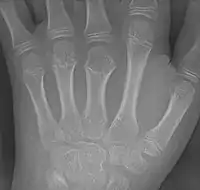

![]() Braquimetacarpia del tercer metacarpiano. | ||

Generalmente, cuando la braquimetacarpia es causa de la braquidactilia, la altura pequeña del metacarpo afectado es la que causa la falta de altura del dedo arriba del metacarpo, ya que en radiografias de dedos aparentemente cortos con braquimetacarpia, se puede observar que las falanges del dedo afectado son de altura normal, sin embargo, la altura del hueso metacarpo abajo de este es anormalmente corta, lo cual también afecta la "altura" del dedo, sin embargo, sí es posible que se presenten la braquimetacarpia y el braquifalangismo juntos.[3]